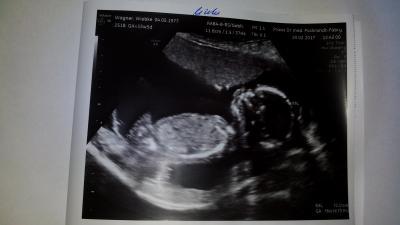

Hallo ihr lieben. Bin auch zurück und die FÄ hat doch kurz geschallt :) Beide Kinder leben, zappeln und sind wohlauf. Es liegt immernoch ca. 1 Woche zwischen den beiden. Das kleine baby hat nun eine SSL von 9,39 cm und das entspricht 15 + 2. Das grössere hat nun eine SSL von 10,31 cm und das entspricht 16 + 1. Ich BIN 15 + 5 Liege also quasi genau dazwischen. Das kleinere ist 3 Tage zurück, das grössere 3 Tage weiter wie ich ausgerechnet bin. Spüre die beiden auch. Bin so erleichtert. Beim letzten mal war das kleinere SSL 5,87 cm und das grössere 7,4 cm. Das kleinere wäre dann ca. 3,4 cm gewachsen und das grössere ca. 3,1 cm gewachsen. So wie es aussieht holt das kleinere wirklich langsam etwas auf und es ist vermutlich, so wie meine Frauenärztin und ich vermuten, einfach genetisch bedingt dass der grosse unterschied besteht. Mein Vater und seine Kinder sind alle klein (ich selbst bin voll ausgetragen mit Nichtmal 45 cm und keinen 2500 Gramm auf die Welt gekommen , bin mein leben lang auch so "mikrig" geblieben) der Bruder meines Vaters und seine nachkommen sind alle seeehr groß (Männer im schnitt 1,85 +/- 5-10 cm und die Frauen alle über 1,70). Mein großer Sohn kam pünktlich geboren ohne SS Diabetes mit 55 cm und 4290 Gramm auf die Welt, die kleine von mir kam einen Tag nach et und war 49 cm und hatte nur 2940 Gramm. ICH bin nun etwas entspannter und denke das ich nun einmal einfach n Kavenzmann wie meinen Sohn bekomme (wir vermuten schon von Anfang an das ist ein Mädchen) und einen kleinen "Schmalhans-Plattfuss" wie meine Tochter bzw. Ich (wir vermuten das wird ein Junge). Die Frauenärztin sieht das auch so dass es genetisch sein muss. Aber es muss halt im Auge behalten werden. Zum Geschlecht hab ich leider noch gar keine Prognose... Ich hoffe die endgültigen Testergebnisse von den Mutterkuchen Punktionen kommen nun und geben die Geschlechter bekannt oder dann der Ultraschall am Freitag in der pränatal Praxis... Da muss ich schon um 9 Uhr sein. Werd spätestens um 7 hier los fahren, muss mit bus und Zug fahren diesmal. Aber Geschlecht hin oder her, ich bin erstmal sehr erleichtert dass das kleine scheinbar etwas aufgeholt hat und sonst alles gesund ist :) Lg

Bild zu Auch zurück von der Frauenärztin - Forum für August - Mamis

Ja, sieht so aus. Das 2. Bild wollte wohl nicht, Versuche es nochmal

Toll das es den beiden so gut geht! Süße Bilder :)

Tolles Bild meine Liebe! Ich freue mich sehr für dich, dass es den beiden Zwergen gut geht und die dich gut entwickeln!